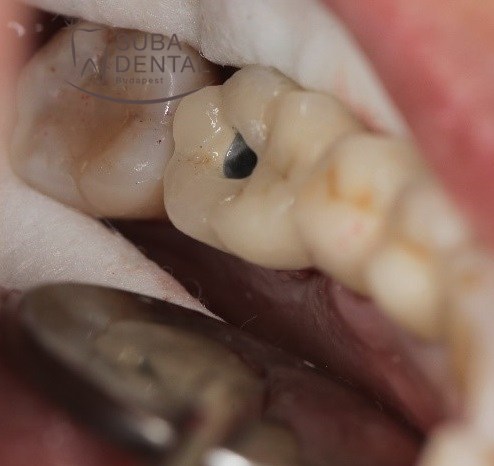

La couronne définitive transvissée sur l’implant dans la bouche

Le trou de la vis qui tenait la couronne a été fermé par une obturation blanche qui correspondait a la couleur de la couronne.

Le trou a été fermé par une obturation afin d’obtenir le meilleur résultat esthétique.